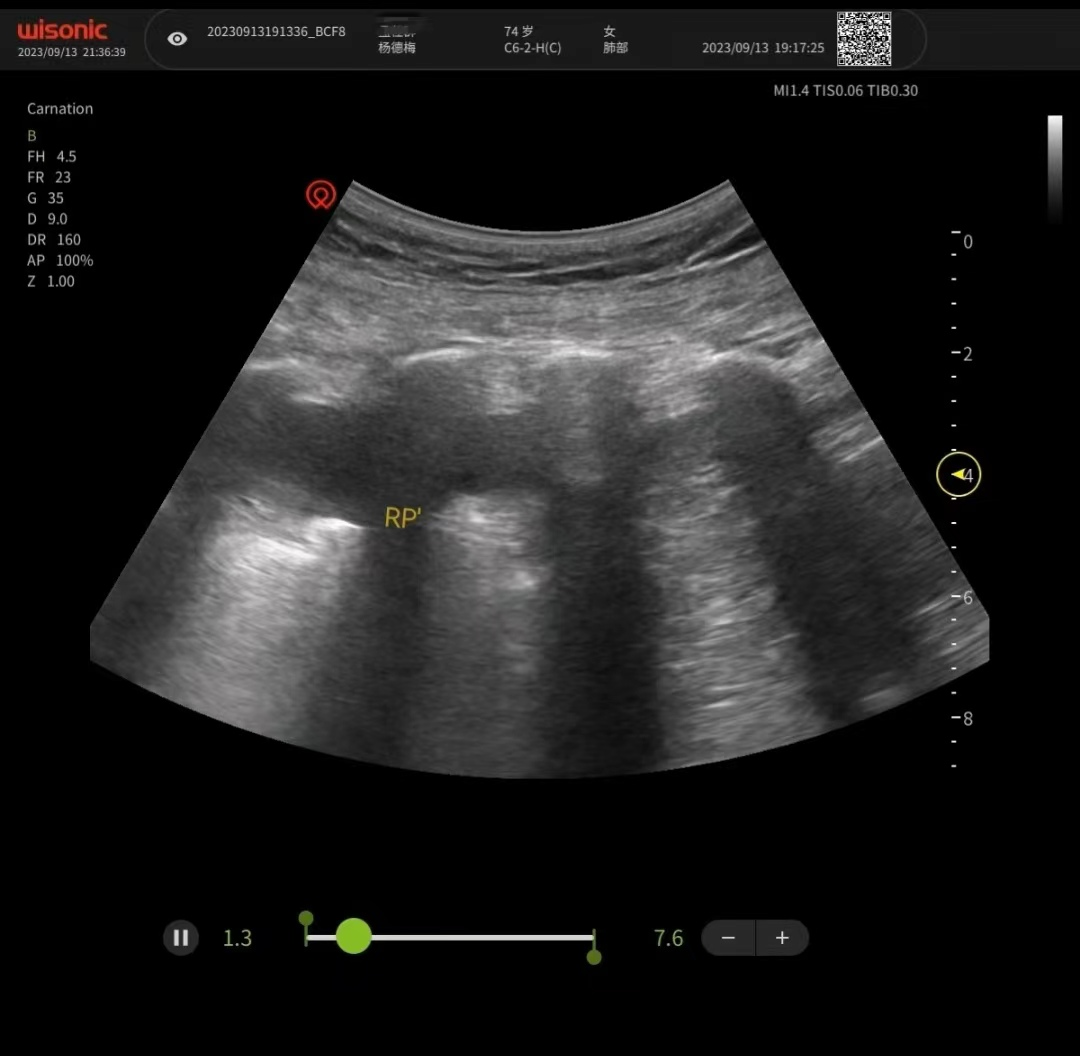

肺部超声

肺部超声可以在床边进行操作,是一种没有辐射、没有创伤,且不要求患者憋气的检查方法。可以多方位、多角度实时动态反复检查,进而在超声机上呈现不同的图像。通过分析,对疾病做出判断。对需要监护的病人来说,非常便捷,可以实时观察、对比治疗效果,提高了重症患者的救治水平和护理能力。

治疗后肺部超声